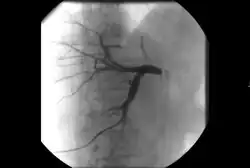

Angiography: Sometimes referred to as traditional angiography, catheter angiography or digital subtraction angiography (DSA). A small needle is inserted into a blood vessel, then exchanged for a catheter over a wire. The catheter is directed at the vessel to be studied, and contrast is directly injected to evaluate the lumen under video X-ray. This is an older technique than modern CT angiography or MR angiography, but provides unique advantages. With a catheter in place, provocative maneuvers can be performed such as breath holds or instillation of vasodilators, to evaluate a patient's blood flow dynamically. This can reproduce symptoms and identify functional abnormalities in a vessel that a static CT or MR imaging cannot.[80][81] Angiography provides the basis for all endovascular therapy.

There are several systems for staging PAD, but an often used scale is the revised Rutherford classification.[76][89] Plaque and blood flow can be evaluated using ultrasound, CT angiography, MR angiography, and catheter-based angiography to establish anatomic segments of disease. The severity of ischemia can be evaluated by correlating symptoms and non-invasive physiologic vascular studies including toe pressures, TCPO2, and skin perfusion studies.